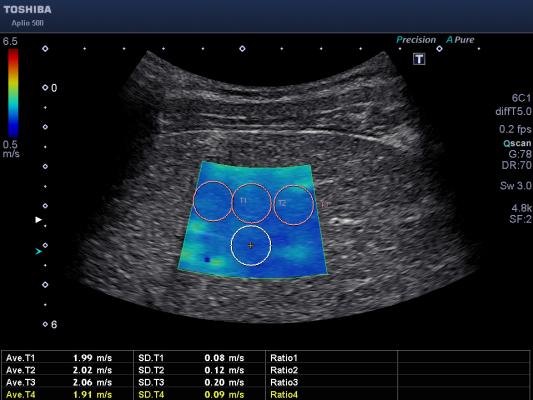

Ποια είναι η βιολογική ηλικία της καρδιάς και του εγκεφάλου σας; Τι δείχνει νέα εξέταση

Γιατί είναι σημαντικό να γνωρίζετε τη βιολογική σας ηλικία; Κάποια όργανα γερνούν ταχύτερα από άλλα και αυξάνουν τον κίνδυνο εμφάνισης ορισμένων ασθενειών με τα χρόνια.